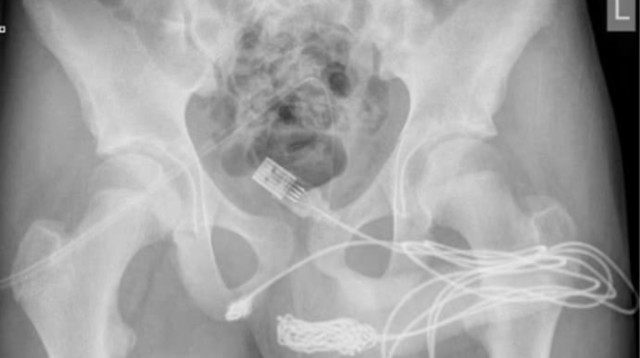

ניסה למדוד את איבר מינו עם כבל USB - וזה נגמר רע